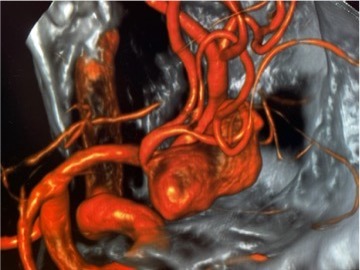

Gehirnaneurysma (Clip, Coil, Flow Diverter)